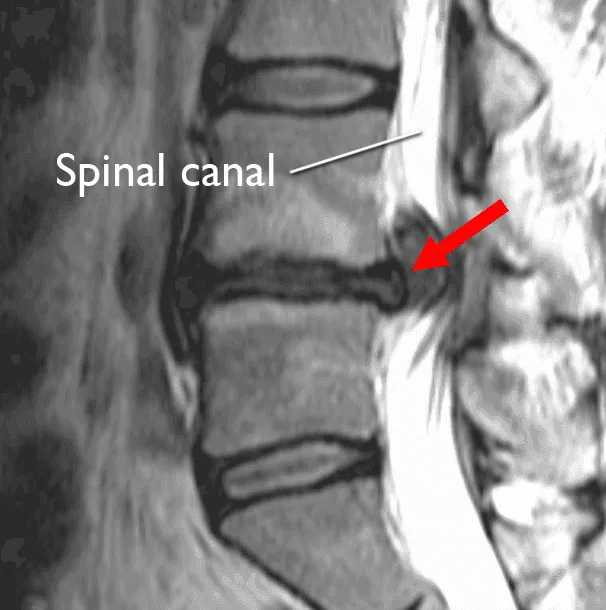

While clinical examination provides valuable information, imaging studies are essential for confirming the diagnosis and guiding treatment decisions.

- Magnetic Resonance Imaging (MRI): MRI is the gold standard for diagnosing L4-L5 disc herniation. This technology provides exquisite detail of soft tissues, including the intervertebral discs, nerve roots, and surrounding structures. MRI can reveal the precise location and size of the disc herniation, the degree of neural compression, the presence of annular tears, other degenerative findings at adjacent levels, and spinal canal dimensions.

A critical point that cannot be overstated: not all disc abnormalities seen on MRI are symptomatic. Research consistently shows that a significant percentage of asymptomatic individuals have disc bulges or even small herniations on MRI. This is why correlation between imaging findings and clinical symptoms is essential. Your physician must determine whether the imaging findings explain your specific symptom pattern.